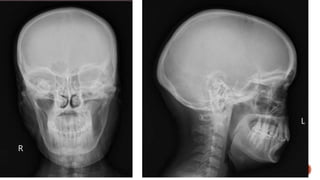

 AP and lateral radiographs of the skull show a well defined lytic lesion involving

the left ramus of the mandible causing scalloping of the medial margin with

associated soft tissue swelling.

MANDIBLE XRAY

 Axiolateral oblique

 The patient is seated upright

 Give true lateral position

 Slightly extend the neck

 Tilt the head towards the detector

 Central ray 25-30 degree cephalad

 The patient is stationary, while the x ray source and the film rotates.